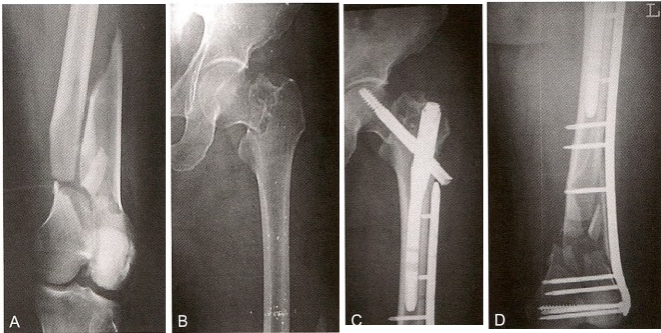

对于累及股骨远近端的骨折,根据骨折类型及粉碎程度可选择适当的组合式内固定,包括髓内钉一体化固定以及髓内钉+锁定钢板。股骨近端骨折合并有股骨远端骨折,用一种内固定方法很难完整固定。这类骨折称连枷骨折(Lambiris IV型)(图12-14A 、B) 。近端用髓内 钉固定,远端用钢板固定(图12-14C 、D) 。术后2年检查,示骨痂明显生长(图12-14E 、F)。

图12-14 对股骨连枷骨折采用髓内钉及钢板固定。A.股骨近端骨折;B. 股骨干、远 端骨折;C.近端髓内钉固定;D.远端钢板固定;E、F.术后2年所见